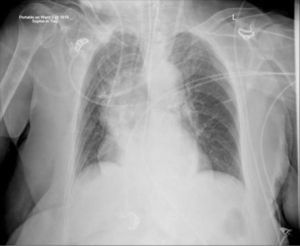

IMAGENOLOGÍALos catéteres centrales de uso corto son insertados habitualmente sin imágenes en tiempo real, con una radiografía de Tórax posterior para confirmar su ubicación. Los extremos distales de los catéteres se movilizan con los cambios de posición (desde el decubito hasta estar sentado y en posición de pié) y con la respiración profunda20. La inserción guiada por electrocardiografía o los sensores electromagnéticos se están utilizando cada vez más, sin embargo no confirman si la punta del catéter está en posición venosa, arterial o en mediastino, así como tampoco podemos saber si el catéter está enroscado.

Ante esta situación, los catéteres son fácilmente reconocidos como mal colocados y generalmente no se necesita el consejo de un especialista antes de su revisión, uso o retiro. Los catéteres pueden estar en una posición obviamente incorrecta fuera de la vena o puede parecer que siguen una ruta normal aproximada a través de la radiografía torácica, pero no están correctamente colocados en la vena cava superior. Las imágenes de tomografía computarizada axial muestran que no se pueden distinguir un catéter en una imagen plana el espacio pleural derecho, los vasos mamarios internos derechos, el sistema ácigo, la aorta ascendente o el mediastino (Figura 8). La radiografía torácica sólo puede confirmar el paso del catéter central, plegamientos de éste o complicaciones de procedimiento.